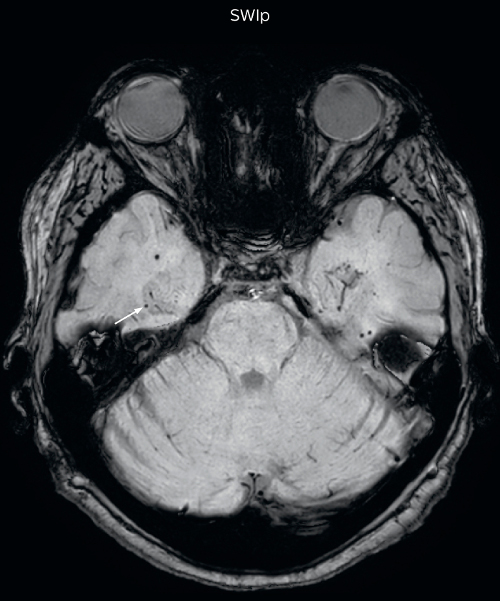

Hemosiderin foci in brain

Gradient echo imaging and SWIp are compared in a patient with radiation-induced foci of hemosiderin deposition. A greater number of small foci is seen on the SWIp image. Ingenia 3.0T

“With SWIp we are basically looking for blood byproducts. It is a sensitive method for visualizing small lesions containing deoxygenated blood. In our comparison, SWIp images are vastly better than gradient echo imaging, there’s no question of that anymore.”

“We find the SWIp images very useful in three areas in particular. In patients with a history of hypertension, it offers clear visualization of hemosiderin deposition from hypertensive hemorrhages. We certainly see a greater number of foci of hemosiderin deposition on the SWIp images than on the T2* gradient echo images. In addition, it also helps us visualize amyloid depositions in patients with amyloid angiopathy.”

Dr. Nickerson mentions trauma patients are the third large area where SWIp is useful. “We benefit from SWIp in trauma patients, certainly in cases with diffuse axonal injury and shearing injuries. Our study shows that SWIp usually provides us better visualization,” he says.